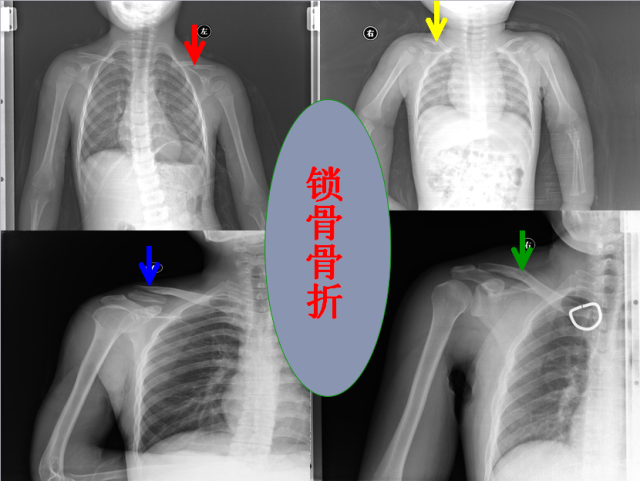

骨折篇

01

定义:骨折{Fracture}是指骨的完整性和连续性的折裂或粉碎。包括创伤性骨折、疲劳性骨折和病例理性骨折。 临床上以创伤性骨折*常见。